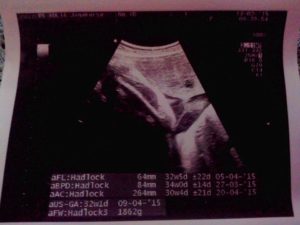

Tanggal 13 Februari 2015, hari ini jadwal nya control si jagoan kembar ke dokter. Dan ini udah masuk usia kehamilan yang ke-34 minggu. Posisi kepala nya sudah di bawah semua. Posisi plasenta nya juga tidak menutupi jalan lahir. Cuma saat itu masalah nya ada di berat badan. Ternyata berat jagoan yang pertama jauh lebih besar dibandingkan dengan berat jagoan yang kedua. Berat jagoan pertama 2.4 Kg sedangkan berat jagoan yang kedua Cuma 1.6 Kg. Saat itu yang di khawatirkan dokter adalah TTS (Twin to Twin Transfusion Syndrome), tapi kalopun terjadi itu kemungkinan nya kecil, karena si jagoan ini masing2 memiliki plasenta. Dengan kata lain plasenta nya sendiri2. Masih belum tau juga saat itu apa penyebab jarak yang terlalu jauh untuk berat nya.

Ini dia Foto USG saat si Jagoan Kembar 34 Minggu